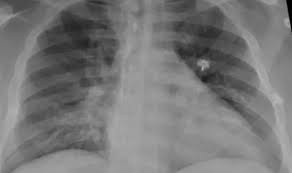

La neumonía bilateral “es una de las mayores complicaciones de los pacientes con Covid, es una enfermedad que afecta los dos pulmones. En casos graves debe internarse y a veces puede ser causa de muerte”, alerta Ana Putruele, jefa de la División de Neumología del Hospital de Clínicas.

En la actualidad este tipo de neumonía en general se ve en casos de coronavirus y constituye el 80% de las internaciones. También se presenta en menores de 2 años ,en mayores de 65 y en portadores de enfermedades crónicas, cardíacas y asociadas a tabaquismo suele generar riesgo de mortalidad llevando a insuficiencia respiratoria severa o distress respiratorio que requiere de oxigenoterapia o si es muy grave asistencia respiratoria mecánica”, comenta la profesional.

La neumonía es una infección que afecta a los pulmones, de forma aguda, generando síntomas como fiebre, tos, dolor torácico y falta de aire. “Cuando baja la temperatura se duplican o triplican las posibilidades de infecciones pulmonares. Por otro lado, las personas tienden a estar más tiempo en ambientes cerrados que favorecen la transmisión de enfermedades virales”, comenta Putruele,